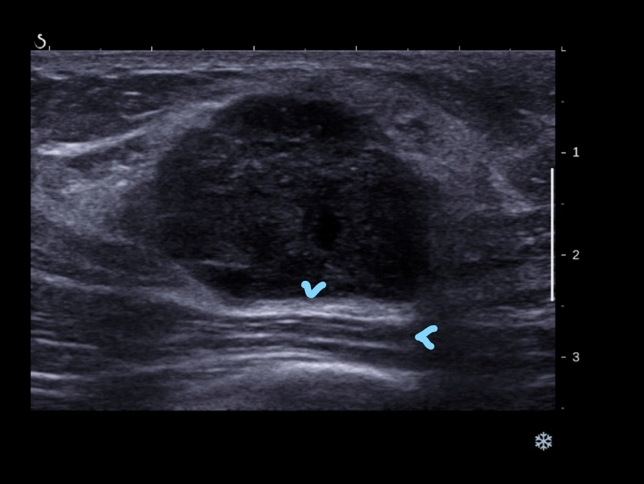

The ultrasound (US) features of breast cancer have recently been shown to have prognostic significance. We aim to assess these features according to molecular subtype. 1140 consecutive US visible invasive breast cancers had US size and mean stiffness by shearwave elastography (SWE) recorded prospectively. Skin thickening (> 2.5 mm) overlying the cancer on US and the presence of posterior echo enhancement were assessed retrospectively while blinded to outcomes. Cancers were classified as luminal, triple negative (TN) or HER2 + ve based on immunohistochemistry and florescent in-situ hybridization. The relationship between US parameters and breast cancer specific survival (BCSS) was ascertained using Kaplan-Meier survival curves and ROC analysis. At median follow-up 6.3 year, there were 117 breast cancer (10%) and 132 non-breast deaths (12%). US size was significantly associated with BCSS all groups (area under the curve (AUC) 0.74 in luminal cancers, 0.64 for TN and 0.65 for HER2 + ve cancers). US skin thickening was associated most strongly with poor prognosis in TN cancers (53% vs. 80% 6 year survival, p = 0.0004). Posterior echo enhancement was associated with a poor BCSS in TN cancers (63% vs. 82% 6 year survival, p = 0.02). Mean stiffness at SWE was prognostic in the luminal and HER2 positive groups (AUC 0.69 and 0.63, respectively). In the subgroup of patients with TN cancers receiving neo-adjuvant chemotherapy posterior enhancement and skin thickening were not associated with response. US skin thickening is a poor prognostic indicator is all 3 subtypes studied, while posterior enhancement was associated with poor outcome in TN cancers.